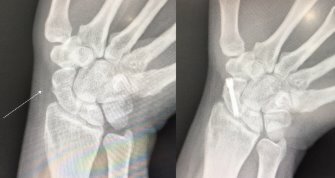

看的出來婆婆很想幫我坐月子,因為他幫我坐月子他比較知道我愛吃什麼,我也能安心地好好坐月子,但幾個月前她不小心跌倒,手掌去撐地造成骨折,到現在還沒完全癒合,我怎麼忍心他再到市場買菜提那麼重,又要備煮煮菜,煮菜真的是很麻煩的一件事情,更怕他又因為煮給我吃傷都一直不會好怎麼辦?又要幫我照顧小孩><